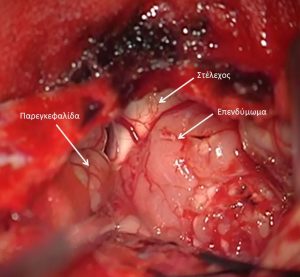

Τα επενδυμώματα ανήκουν στα γλοιώματα και αναπτύσσονται τυπικά εντός ή πλησίον του επενδύματος του κοιλιακού συστήματος του εγκεφάλου. Η πιο συνηθισμένη θέση είναι η περιοχή της παρεγκεφαλίδας (Εικόνα 1 & 2).